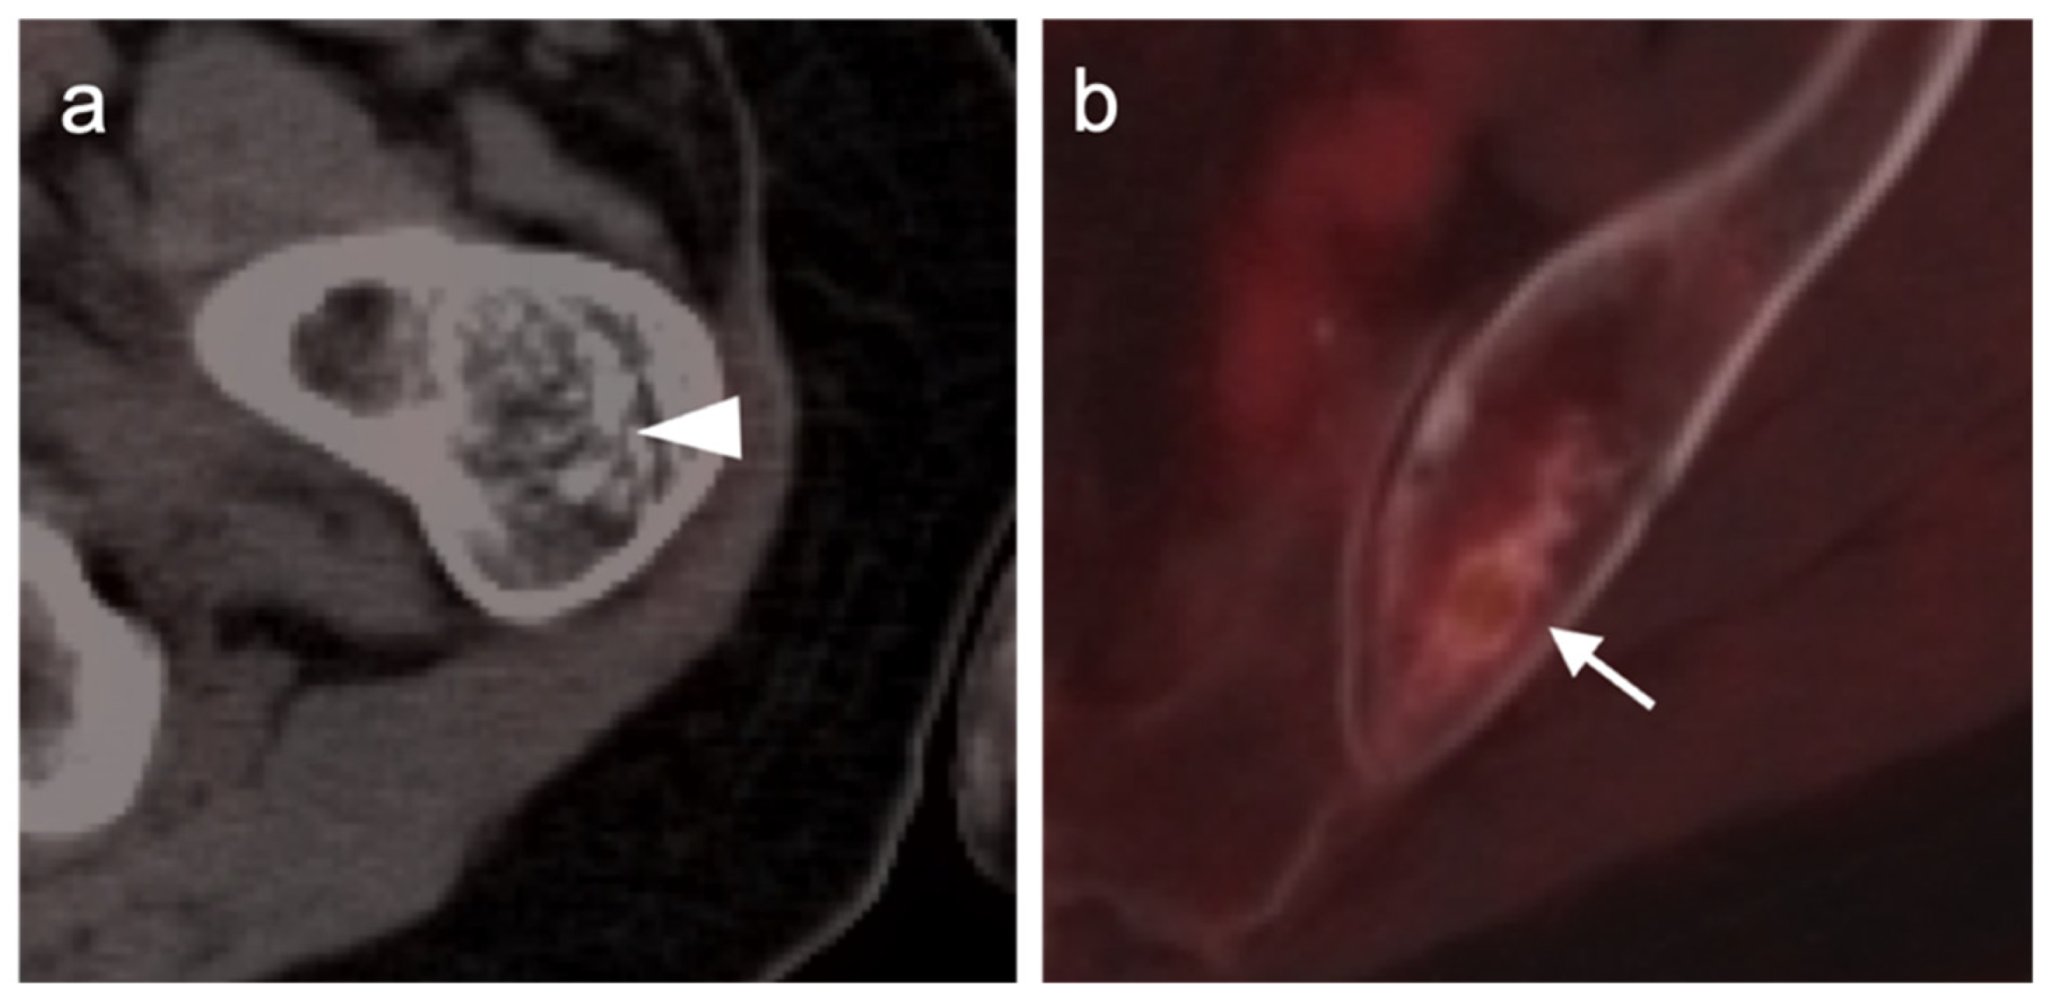

- Broski, S.M.; Johnson, G.; Howe, B.M.; Nathan, M.A.; Wenger, D.E.; Spinner, R.J.; Amrami, K.K. Evaluation of 18F-FDG PET and MRI in differentiating benign and malignant peripheral nerve sheath tumors. Skelet. Radiol. 2016, 45, 1097–1105. [Google Scholar] [CrossRef]

- Li, C.-S.; Huang, G.-S.; Wu, H.-D.; Chen, W.-T.; Shih, L.-S.; Lii, J.-M.; Duh, S.-J.; Chen, R.-C.; Tu, H.-Y.; Chan, W.P. Differentiation of soft tissue benign and malignant peripheral nerve sheath tumors with magnetic resonance imaging. Clin. Imaging 2008, 32, 121–127. [Google Scholar] [CrossRef]